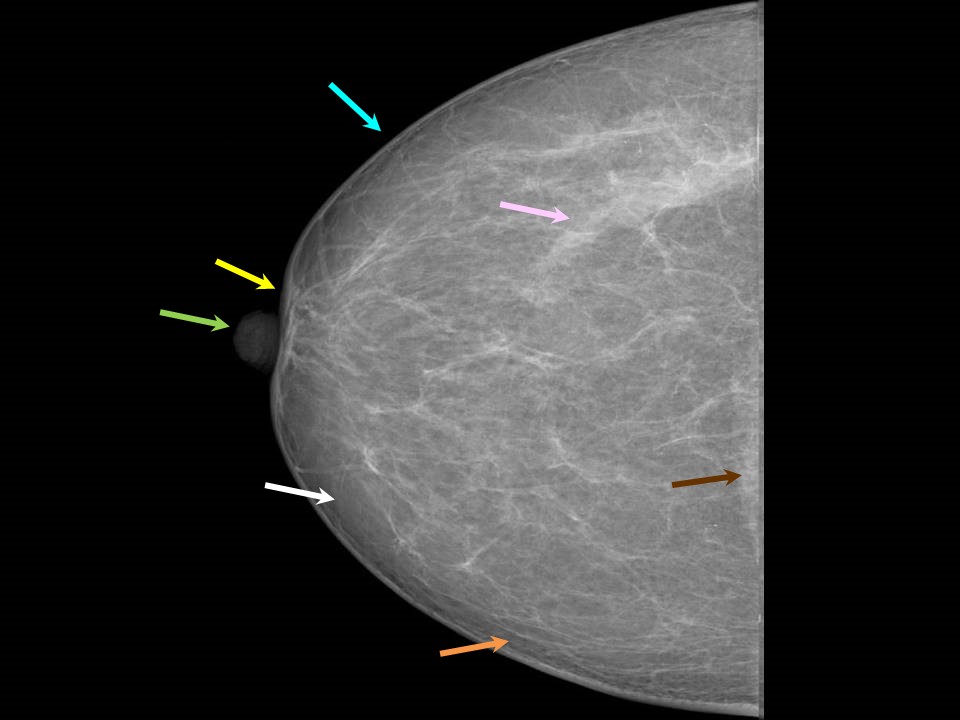

From screening.iarc.fr